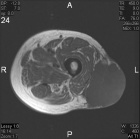

86 year old male with nontender, enlarging left thigh mass

Zoom image: Radiological image Radiological image.